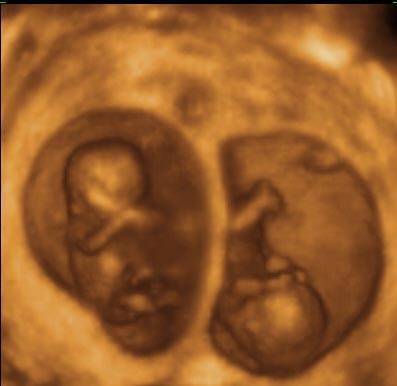

Он там не один

С мальчиками-девочками мы разобрались, а если там двойня или тройня. Имеет ли многоплодная беременность признаки, указывающие на беременность несколькими детьми.

Конечно, носить двойню и более детей не так просто, что проявляется мощной нагрузкой на организм будущей мамочки. Обычно многоплодную беременность отличает раннее начало и длительное течение токсикоза, объяснимое увеличением выработки гормонов. Имеет многоплодная беременность признаки и другого рода: быстрорастущий животик, очень быстрый набор веса, повышенная сонливость всю беременность. Отмечается ярко выраженный синдром постоянной усталости, при котором обычные нагрузки становятся подвигом и даются очень тяжело, даже подъем по ступеням приводит к жуткой отдышке.